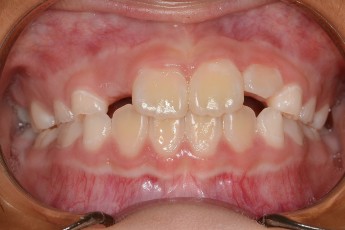

BEFORE & AFTER